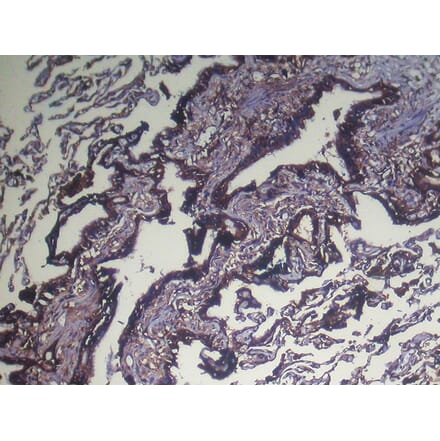

Immunohistochemistry - NUDT4 Antibody from Signalway Antibody (42944) - Antibodies.com